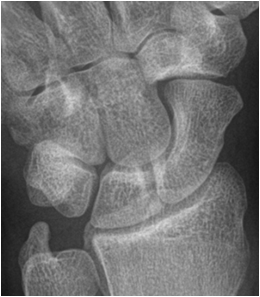

In assessing trauma two perpendicular plains are mandatory. In anatomic areas where this is not possible or helpful (pelvis, shoulder) additional oblique projections are produced. If initial films do not show a fracture despite strong clinical suspicion, the affected extremity should be immobilized, and a repeat study performed after 8 – 10 days. These delayed images will usually depict fracture lines better due to bone absorption during fracture healing. MR images can also be obtained to detect occult trauma early.

Fig. 7. Patent with suspected scaphoid fracture. The wrist film and the scapoid series did not show a definite fracture line. A faint line is seen in the proximal third of the scaphoid. MR imaging of the wrist reveals a bone marrow edema and fracture indicated by a low signal area on a T1 weighted image.